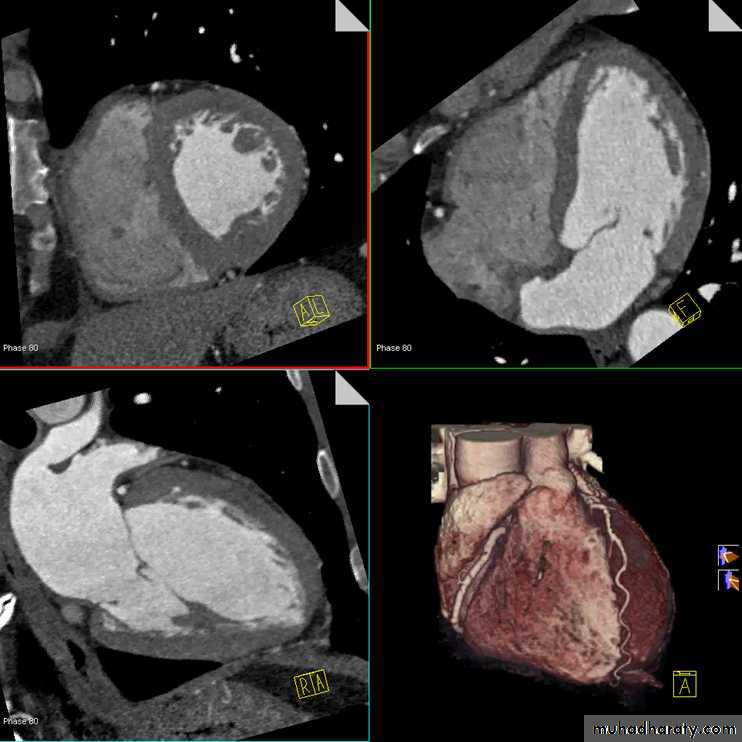

MDCT applications including:

• CT angiography: coronary, cerebral, carotid, pulmonary, renal, visceral, peripheral

• Cardiac CT, including CT coronary angiography and coronary artery calcium scoring